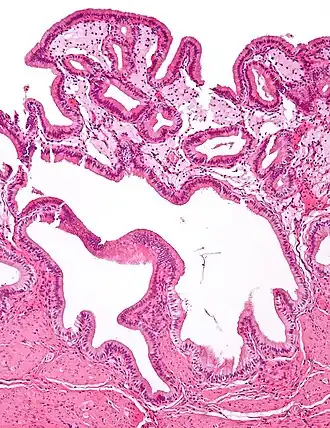

Micrograph of cholesterolosis of the gallbladder